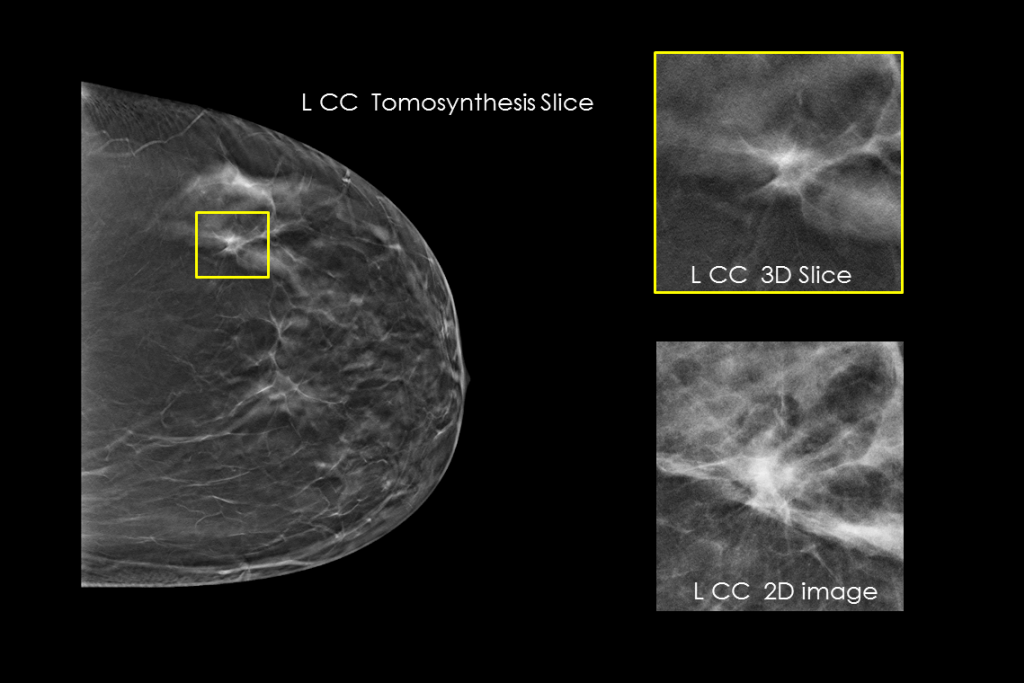

Clinical images of breast scan mammography

Clinical images of breast scan with suspicious Lesion

Clinical images of breast scan

Clinical images of breast scan with fatty breast